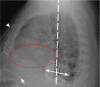

Implanted cardioverter-defibrillators can prevent sudden cardiac death in at-risk patients. In comparison with conventional transvenous systems, entirely subcutaneous implantable cardioverter-defibrillators have produced similar reductions in the rate of sudden cardiac death but with fewer sequelae. An infrequently reported drawback of subcutaneous devices, however, is the potential for generating attenuation artifact during nuclear myocardial perfusion imaging. We had concerns about potential attenuation artifact in a 65-year-old man with coronary artery disease but found that having positioned the pulse generator in the midaxillary zone avoided problems.